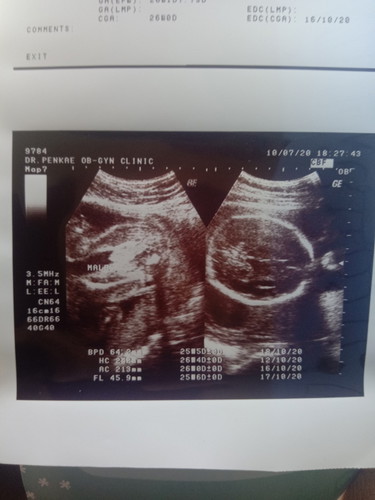

แม่ๆค่ะเป็นผู้หญิงหรือผู้ชายค่ะ

เห็นบ้านอื่นจู๋ยาวกว่านี้กลัวหมอซาวด์ผลาดหรือแม่คิดมากไปเองค่ะ😂😂😂😂อายุครรภ์ตอนซาวด์26สัปดาห์ค่ะ

น่าจะชายนะคะ